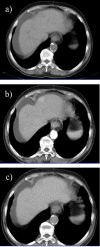

Hepatocellular carcinoma is a major health issue, ranked the fifth most common tumor and currently being responsible for a third of the cancer-related deaths globally, with an ever-increasing number of fatalities. Current advances in contrast-enhanced imaging techniques such as contrast-enhanced ultrasonography, multi-detector computed tomography and diffusion-weighted magnetic resonance imaging are improving the rate of hepatocellular carcinoma diagnosis. Contrast-enhanced ultrasonography has widely become the first choice in liver tumor assessment, as it is faster, simpler and safer than other forms of diagnostic imaging. On the other hand, cross sectional computed tomography is frequently employed when a hepatic formation is suspected of malignancy and allows a more accurate characterization of lesions through multiphasic multi-detector computed tomography technology. Diffusion weighted magnetic resonance imaging represents another addition to the wide range of diagnostic and prognostic techniques available for patients with hepatocellular carcinoma and is currently regarded as one of the best tools for the characterization of these lesions. Furthermore, groundbreaking biomarkers for hepatocellular carcinoma are being discovered, although alpha-fetoprotein remains one of the most frequently used serum test in the early stages. Nonetheless, further advances are required for the detection of small liver carcinomas.